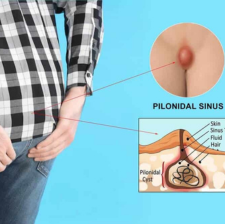

Pilonidal Sinus

An abnormal skin growth located at the tailbone that contains hair and skin.The cyst is usually located near the tailbone and can become easily infected.

Symptoms of an infected cyst include pain, reddened skin or drainage of pus or blood.

Treatment involves drainage and surgical removal of the cyst.